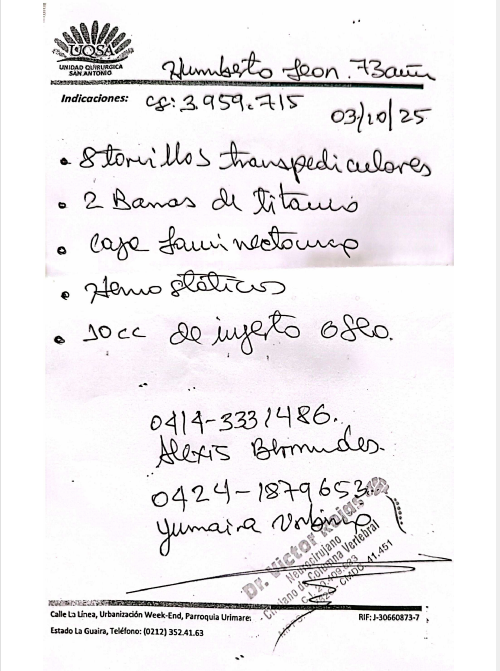

Plan terapéutico: Cirugía propuesta: Abordaje dorsal posterior con fijación mediante tornillos transpediculares (8 tornillos poli-axiales). Colocación de 2 barras de titanio y caja intersomática.Exéresis (retiro) de la lesión tumoral. Pleurostomía (drenaje pleural). Estudio anatomopatológico de tejido óseo obtenido.